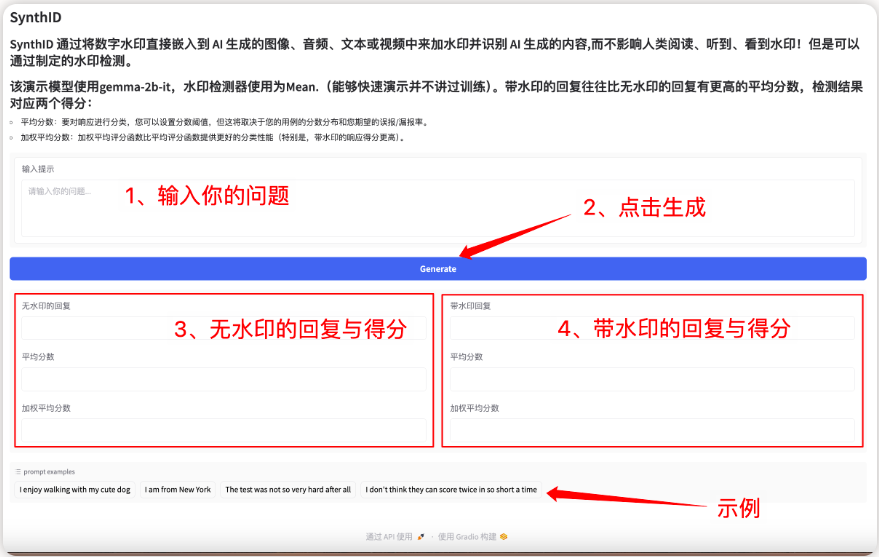

5.ROCOv2 radiology 多模态医学图像数据集

ROCOv2 数据集融合了放射学图像与相关的医学概念和描述,包含了超 7 万张放射学图像,涵盖多种临床模式、解剖区域和方向性(针对 X 射线),每张图像都有相应的医学概念说明。

直接使用:https://go.hyper.ai/XgqCa

数据集图像示例

4. 含 284 个数据集,覆盖 18 项临床任务,上海 AI Lab 等发布多模态医疗基准 GMAI-MMBench

上海人工智能实验室等多家科研单位提出了 GMAI-MMBench 基准,覆盖全球的 284 个下游任务数据集,包括 38 种医学影像模态、18 项临床相关任务、18 个科室以及视觉问题问答格式的 4 种感知粒度,是迄今为止最全面的通用医疗基准。此外,本文还为大家汇总了其他医学领域数据集,内含一键使用连接。

查看完整报道:https://go.hyper.ai/csr2M